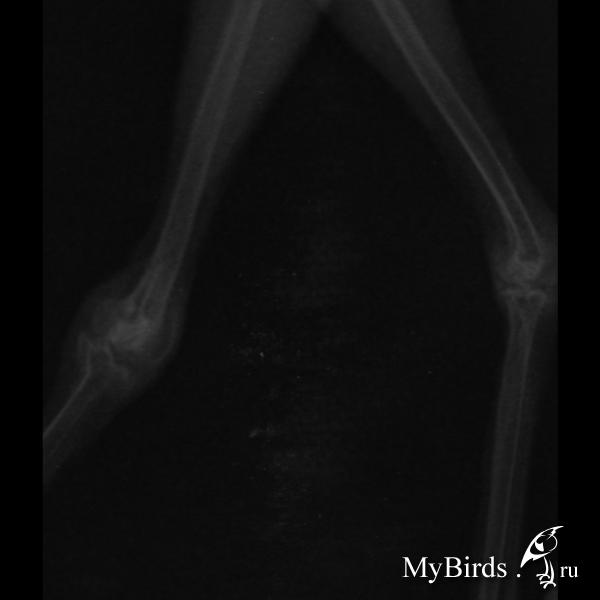

Перелом уже вроде бы сросся, но очень не нравится то, что у него опухший сустав (колено) и плохо сжимает пальцы на больной ноге. Видно что она его тревожит, хоть он на жердочке, хоть бегает по полу. Я так понимаю что это вызвано тем, что сросся неправильно и нагрузка на сустав изменилась, видимо трет где-то сбоку. Что теперь делать вообще не понятно...

Посмотрите рентген, может еще что посоветуете

post-62939-1440962267_thumb.jpg